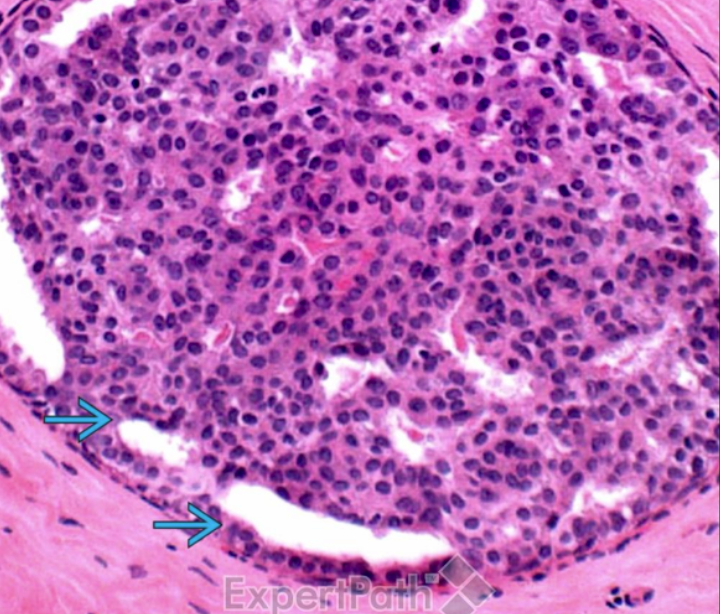

What pathology is indicated here?

Atypical ductal hyperplasia

Note the clonal proliferations that partially fill involved ducts